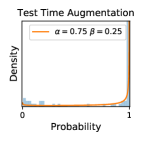

5.1 Distribution of Uncertainty Scores

Distribution of Uncertainty Scores Across Different Severity Levels As explained in Section 3, each uncertainty metric essentially defines an order/ranking among the data points. We conducted an analysis to better understand what data will be assigned high uncertainty under a particular uncertainty metric . Picking out the highest ranked data points (), we calculated the ratio of data points from each SL. Figure 4 summarizes the results as box plots for the Kaggle-DR and the Messidor-2 datasets; additional detailed statistics can be found in Table S.1 in the supplementary materials. From the plot and table, SL1 & SL2 examples account for a higher proportion among the top-ranked uncertain examples across the three ensemble methods. This finding matches our intuition that incipient disease examples (SL1 & SL2) are more likely to be considered uncertain by ensemble methods due to their ambiguity.

In contrast, the MC-dropout method showed the worst overall performance among the three, as it can be seen from the high ratios of SL0 examples among the uncertain negatives in Figure 4. The histograms in Figure 2 provides another perspective to look into the phenomenon, where a decent proportion of MC-dropout model’s predictions on SL0 inputs entailed low confidence (far from 0 or 1), which from another angle explained why MC-dropout was less specific in terms of lower FNP; many no-DR inputs (i.e. SL0) were erroneously assigned high uncertainty by MC-dropout models.

As discussed in Section 5.1 and Section 5.3 in the main paper, the mean metric and the stacking ensemble will have better performance in the precision (specificity) on the ambiguous data. Here, more detailed results are shown in Figures S.3 & S.6 and Table S.1. Figures S.3 & S.4 show the histograms of the uncertainty score for Kaggle-DR and Messidor-2 datasets that are the in-distribution (i.d.) dataset in our experiment and FigureS.5 & S.6 show the histograms for ImageNet and CIFAR-10 datasets, which is the o.o.d. datasets in our experiment. Each group of histograms contains results from the three evaluated ensemble methods (stacking ensemble, MC-dropout and TTA) and the three uncertainty metrics (mean, var and kl). Additional detailed results not displayed in Figure 4 can be found in Table S.1, which shows the proportion of the data of different SLs varies across different . For comparison, we also included in Table S.1 the results from single learners, and the proportions of data of different SLs (before any selection was made).